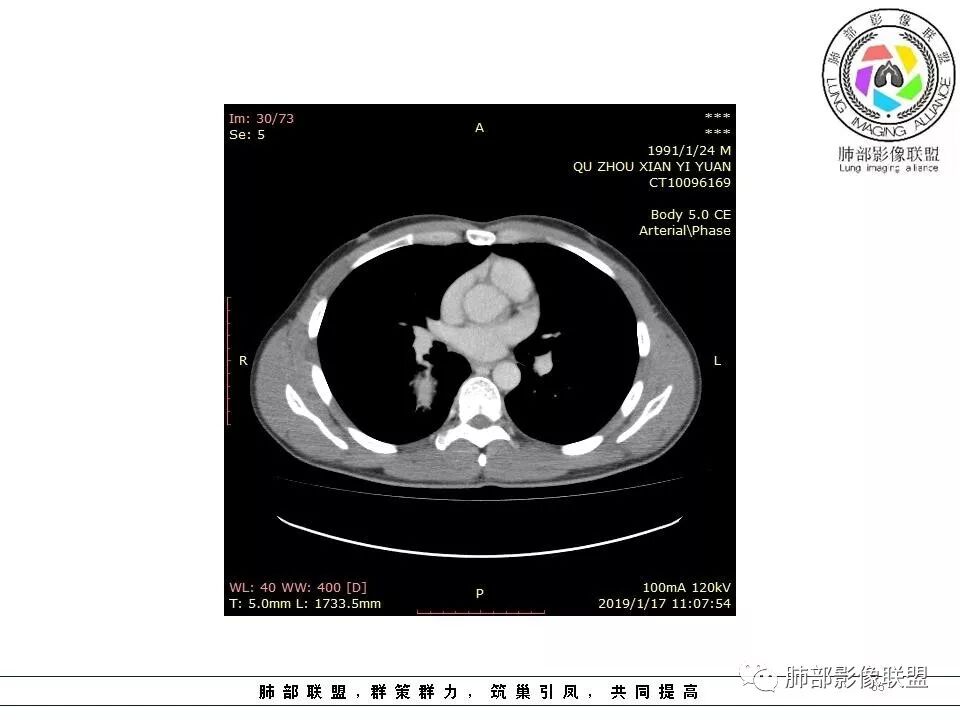

病例小结

1.右上胸内脊柱旁类圆形肿块,质地似乎比较坚实,密度稍显不均,但未显示明确的坏死。

如此密度形态的病灶位于肺边缘首先应当想到孤立性纤维瘤,可相邻胸膜未见明显的异常强化和胸膜方向延伸。

注意所谓“胸膜尾征”的概念及形成机制与“脑膜尾征”是大不相同的。

2.肋间动脉病供血也提示肿块来自后纵隔?

3.相邻椎间孔未见扩大,也未见块影延入椎管,易起自于神经根的鞘瘤似乎找不到支持点。

可惜未提供矢状位骨窗图像,如在肋骨内下缘观察到压迹有助于肋间神经的鞘瘤的判断,这是因为二者之间密切的毗邻关系。

4.静脉期轻度不均匀强化,注意不是环形强化,亦未见明确的“AB区”,这点也不支持神经鞘瘤。临床及病灶轻度强化都不支持副节瘤。

尽管神经纤维瘤的诊断确实有些出乎意外,但病例开阔了我们的视野。

未见多发病灶,患者有无脑内及皮肤病变,资料未能提供,稍显遗憾。